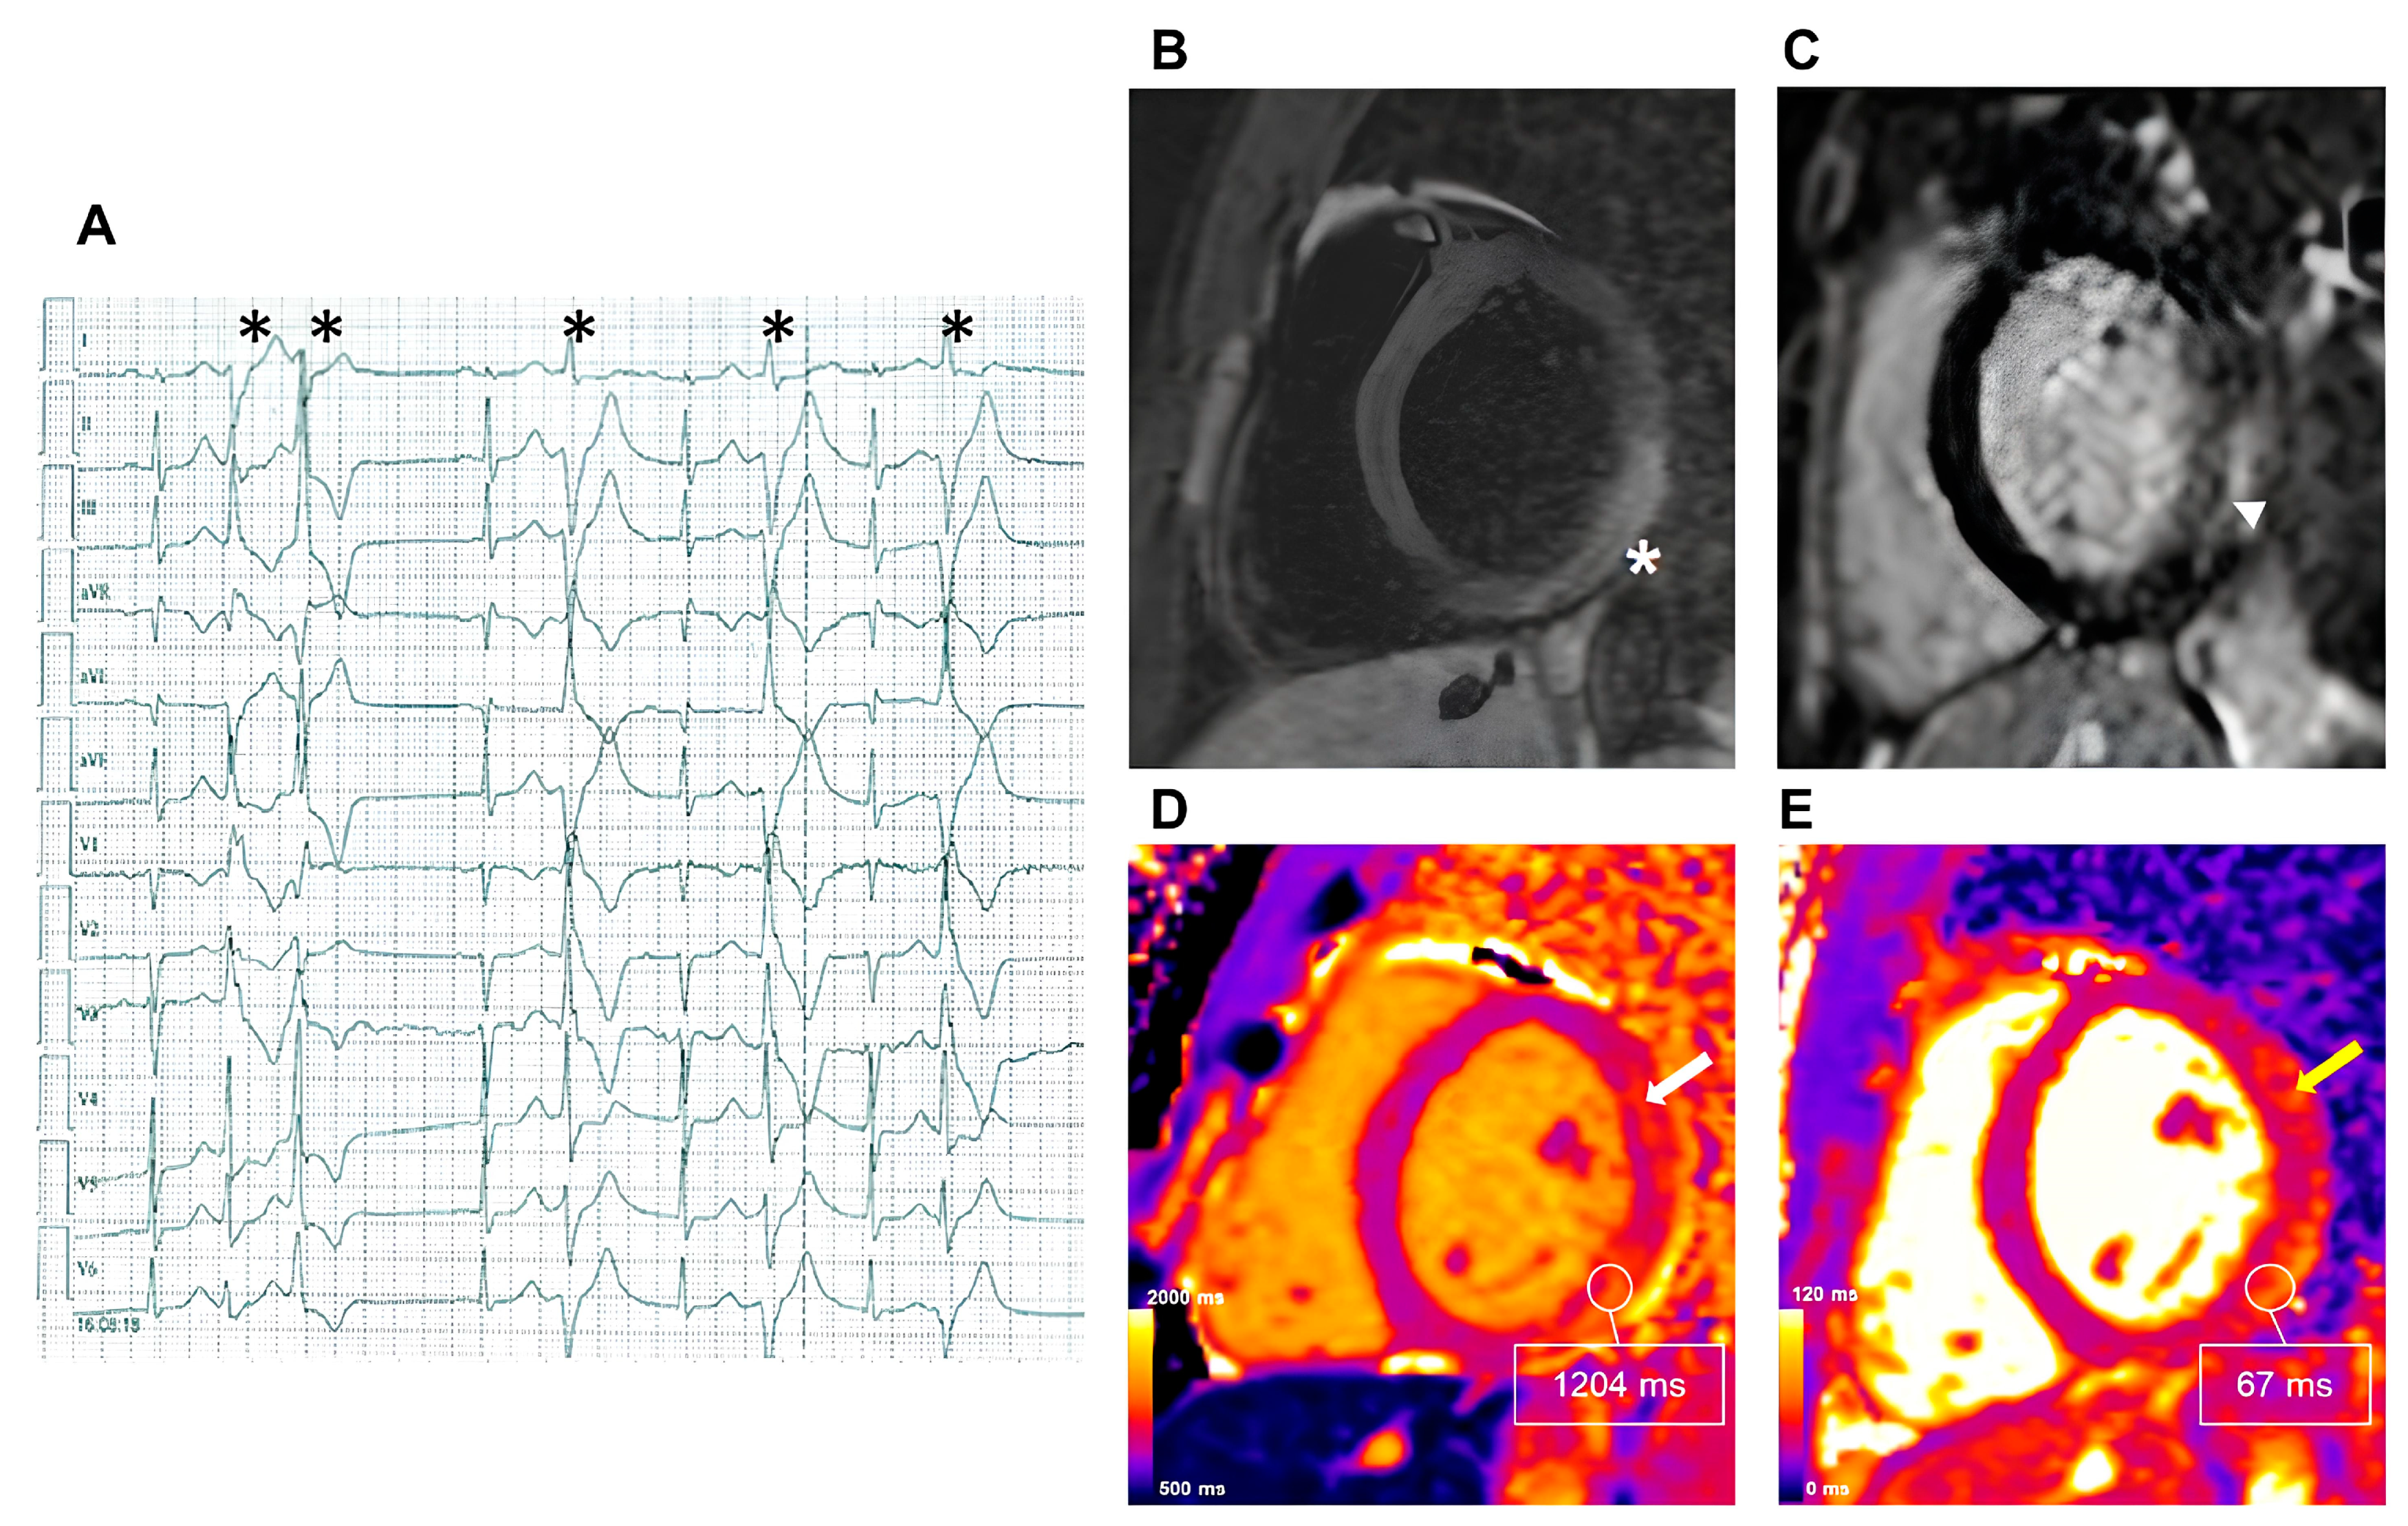

- Dowd, R.; Dhanjal, T.; Schmucki, M.; Kanagala, P.; Khan, J.N. Unique role of cardiovascular magnetic resonance imaging parametric mapping in the diagnosis of arrhythmogenic left ventricular cardiomyopathy. Eur. Heart J. Cardiovasc. Imaging 2021, 22, e96. [Google Scholar] [CrossRef]